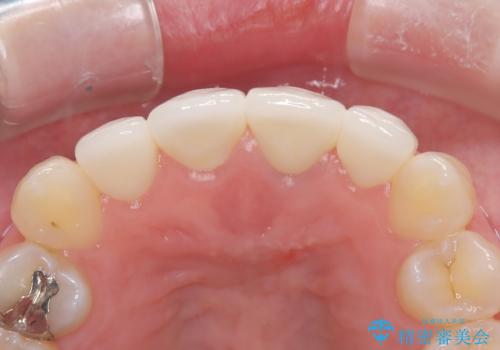

- 「前歯の色が気になる」を主訴に来院された患者様です。前歯が咬んでない開咬という状態のため、矯正治療を勧めましたが、患者様がご希望されなかったためオールセラミッククラウンで治療を行いました。右上1番は、神経の検査の結果、神経が死んでいたため根管療から行いました。左上1番は、金属の土台が入っていたのとラバーダムシートを使用せず根管治療が行われていたため、再度根管治療から行いました。その後ファイバーコアをたてオールセラミッククラウンで治療を行いました。

- 66万円(仮歯1万1千円×4 ファイバーコア2万2千円×2 オールセラミッククラウン スペシャル14万3千円×4)費用は治療当時の料金となります

※今後ホワイトニングを行う予定なので患者様の希望により少し被せ物を白くしています。